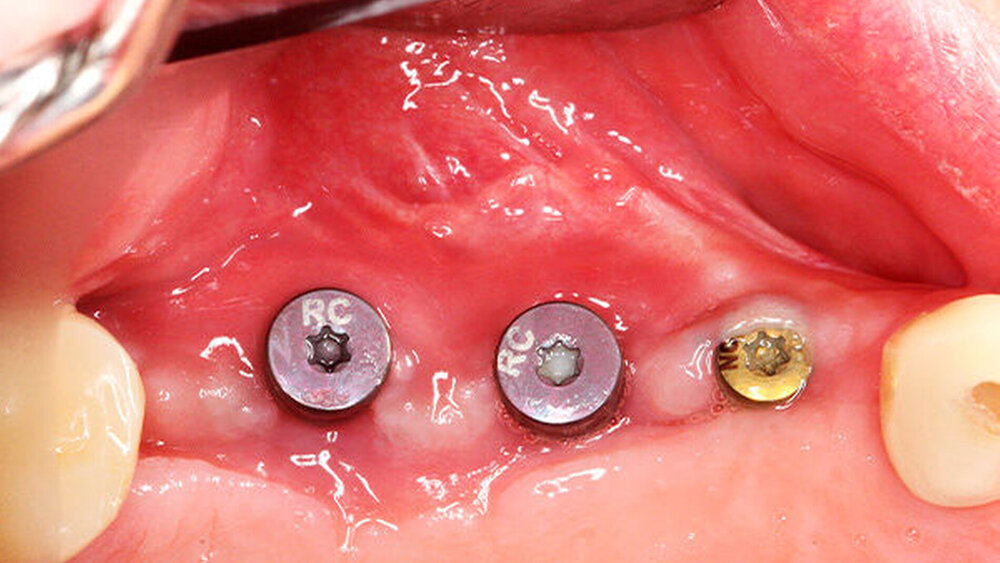

Die Schnittführung wurde nach dem Pillar-Sockel-Design (Blume) vorgenommen. Dabei liegt die Inzision weit im Vestibulum und verbindet zwei vertikale Entlastungsschnitte. Im Gegensatz zu der herkömmlichen krestalen Schnittführung bleibt das Periost über dem augmentierten Bereich damit völlig intakt. Nach der streng subperiostalen Präparation erfolgte die Kontrolle der Passung des CAD/CAM-Blocks. Ein ganz entscheidender Punkt ist, vor jeglichem Kontakt des Blockes mit Blut diesen in steriler Kochsalzlösung und am besten in der PRF-Flüssigkeit zu wässern, sodass sich keine Poren des Blocks mit Blutkoageln verschließen und innerhalb des Blocks ein nicht mit Blut gefüllter Hohlraum bildet. Vor der Befestigung des Blocks wurde die Kompakta des Empfängerbetts mit einer kleinen Kugelfräse mehrfach perforiert um sogenannte Bleeding Points zu setzen, die die Durchblutung des Knochenblocks gewährleisten. Mit zwei Osteosyntheseschrauben mit dem Durchmesser 1,5 mm und der Länge 9 mm wurde der allogene Knochenblock rotationssicher fixiert. Das Augmentat wurde mit einer dünnen Schweinepericard-Membran (Jason membrane, botiss biomaterials GmbH, Vertrieb Straumann) und der PRF-Membran abgedeckt. Der spannungsfreie Wundverschluss erfolgte mit der modifizierten vertikalen Matratzennaht nach Laurrell mit resorbierbarem Nahtmaterial (Vicryl 4.0). Postoperativ wurde ein Oberkiefer-DVT angefertigt. Die Nahtentfernung wurde im Rahmen der Nachsorgeuntersuchung sieben und 14 Tage postoperativ vorgenommen. Nach einer Heilzeit von sechs Monaten erfolgte die Implantation in Lokalanästhesie unter antibiotischer Abschirmung mit 2 g Amoxicillin oral eine Stunde präoperativ. Die Schnittführung erfolgte krestal, und nach subperiostaler Präparation wurde der Knochenblock dargestellt und die Osteosyntheseschrauben wurden entfernt. Danach wurden drei Implantate (Straumann) in den Knochenblock gesetzt und mit 0er-Verschlussschrauben abgedeckt. Die Wundrandadaptation erfolgte mit resorbierbarem Nahtmaterial, das bei der Verlaufskontrolle sieben Tage postoperativ vollständig entfernt wurde. Nach dreimonatiger gedeckter Einheilung wurden die Implantate im Rahmen einer Vestibulumplastik freigelegt. Dafür wurde eine erneute krestale Schnittführung regio 14 bis 17 vorgenommen und ein Splitflap präpariert. Der vestibuläre Wundrand wurde mit Einzelknopfnähten im Vestibulum fixiert. Im Bereich der Implantate wurde der Splitflap perforiert, um die Abdeckschrauben gegen Gingivaformer auszutauschen, und der Bereich des nun freiliegenden Bindegewebes wurde mit einer 3D-vernetzten Kollagenmatrix (mucoderm, botiss biomaterials GmbH, Vertrieb Straumann) abgedeckt. Diese wurde zunächst gewässert, um die Verarbeitung zu erleichtern, und an den Stellen der Gingivaformer gestanzt. Die Nahtentfernung erfolgte neun Tage postoperativ. (Abb. 1a bis 1f).

Nach missglückter Augmentation im rechten Oberkiefer stellte sich ein 42-jähriger Patient in unserer Praxis vor. Für die gewünschten Implantate im rechten Oberkiefer regio 16 und 17 war vertikal deutlich zu wenig Knochen vorhanden. Ein Sinuslift hätte zwar die Höhe des Knochens wieder hergestellt, die prothetische Position der Zahnkronen wäre aber somit in einer Infraokklusion zu liegen gekommen oder die Implanatkronen hätten völlig überdimensioniert werden müssen. Daher entschied sich der Patient für die Rekonstruktion mittels allogenen CAD/CAM-Knochenblocks. Das Prozedere gestaltete sich wie in Fallbeispiel 1. Auch die Einheilzeiten wurden entsprechend eingehalten.